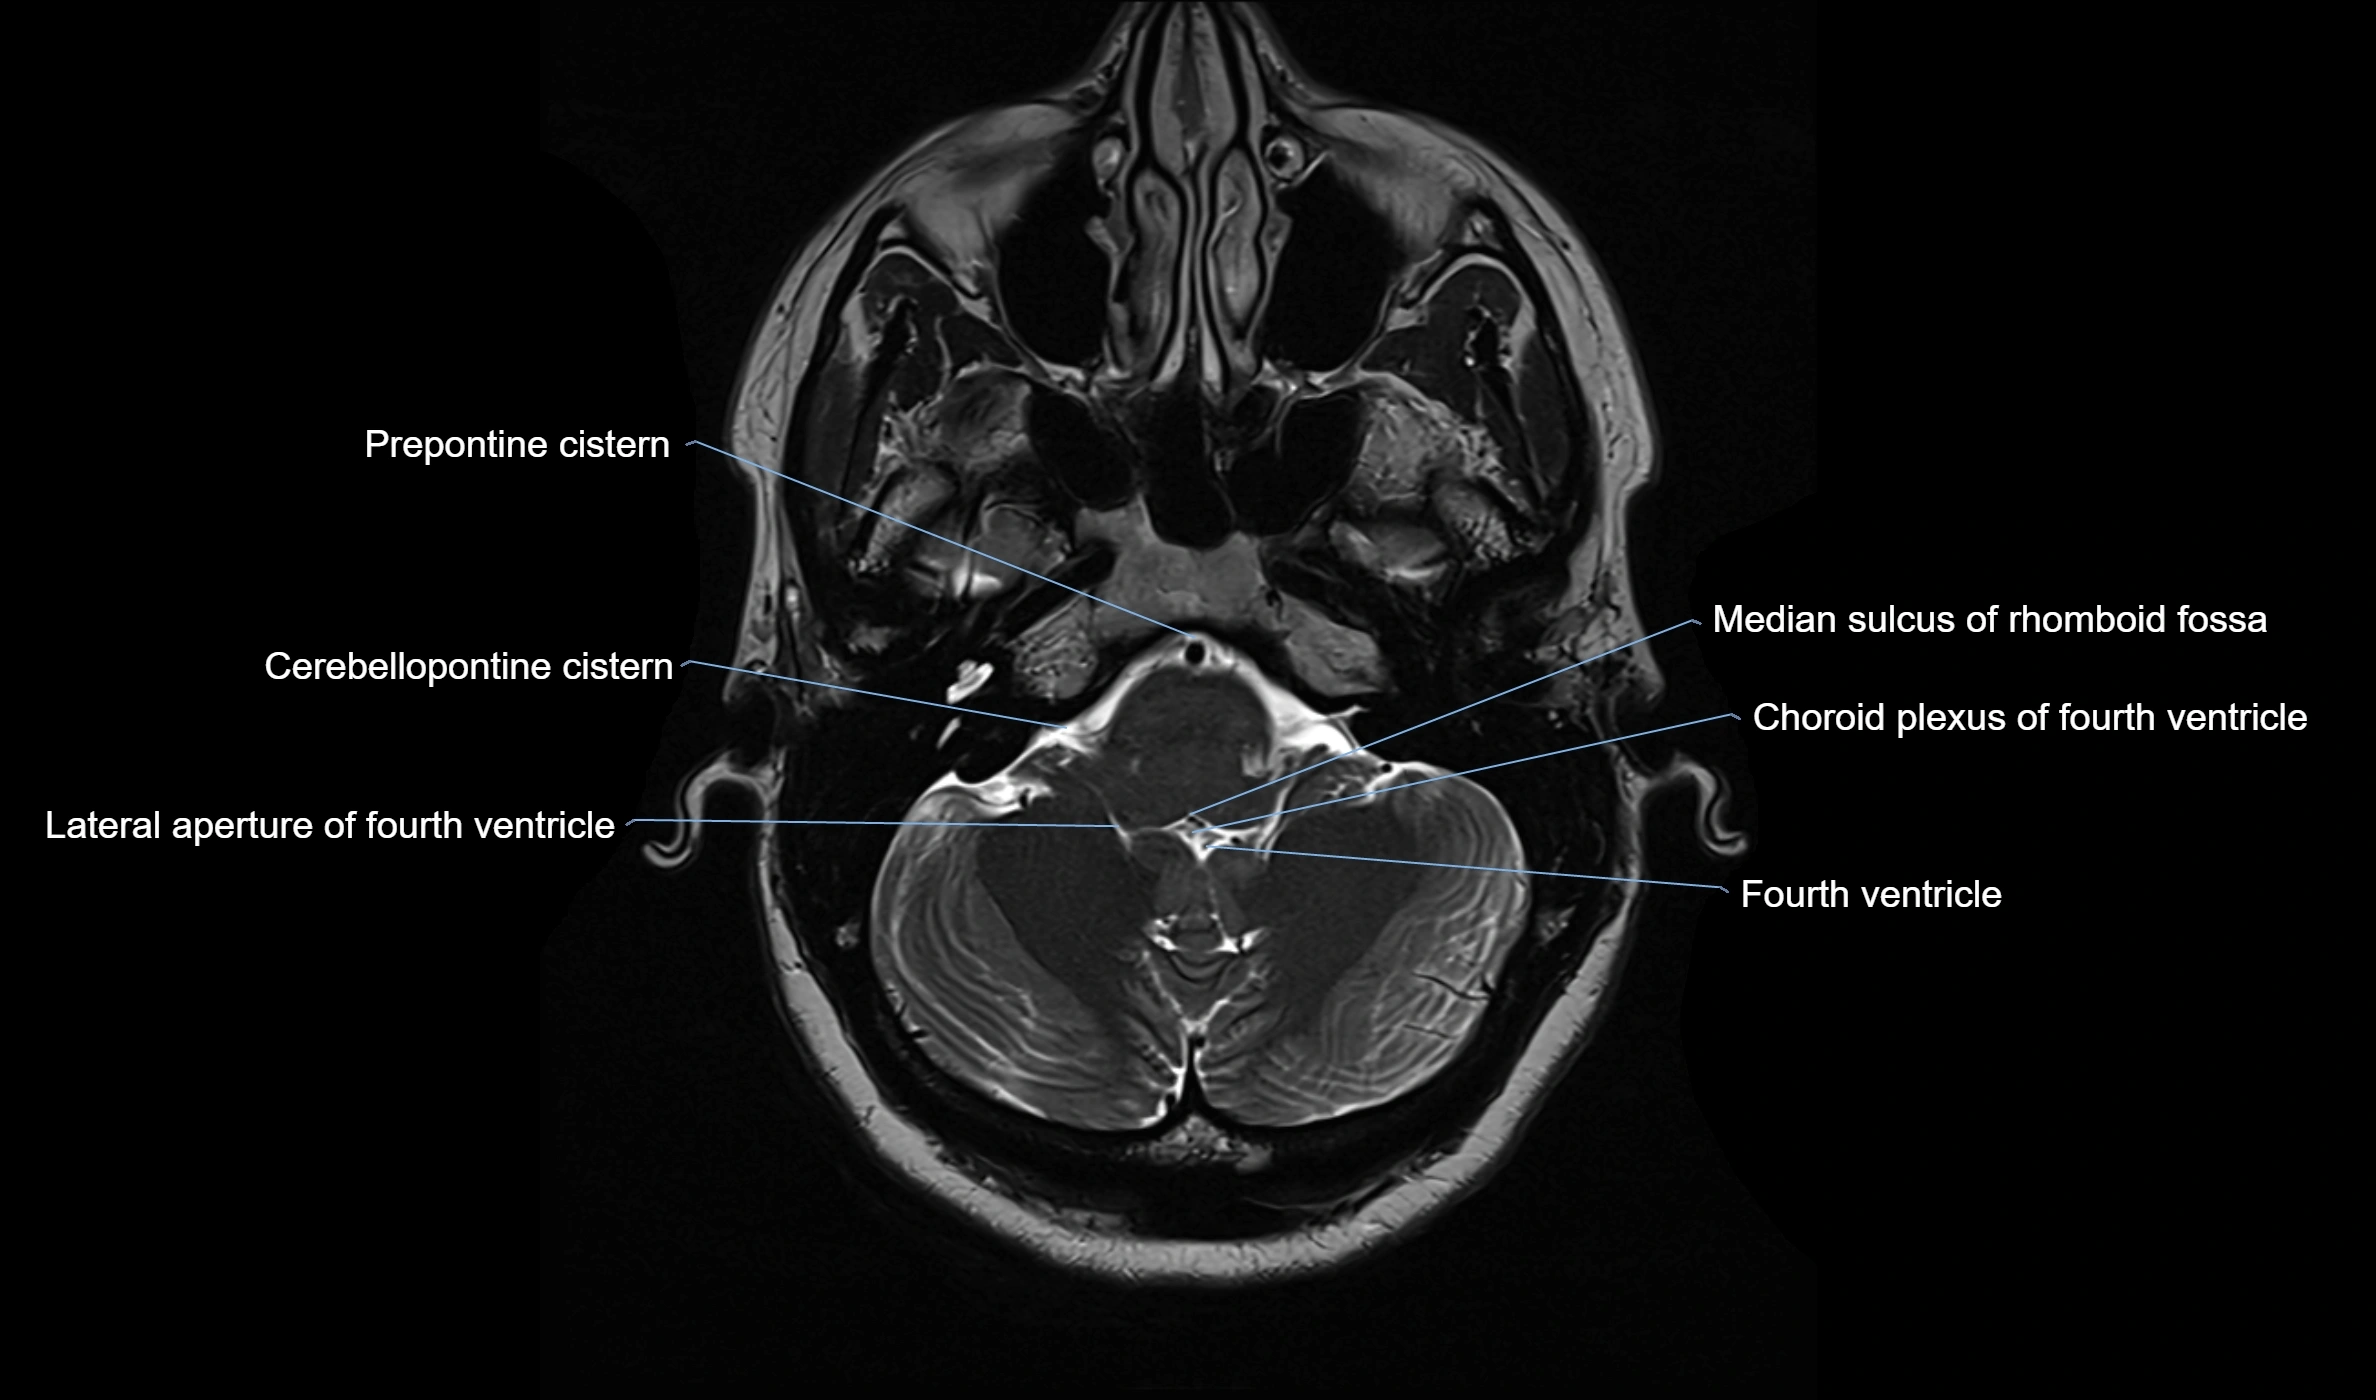

MRI images

image